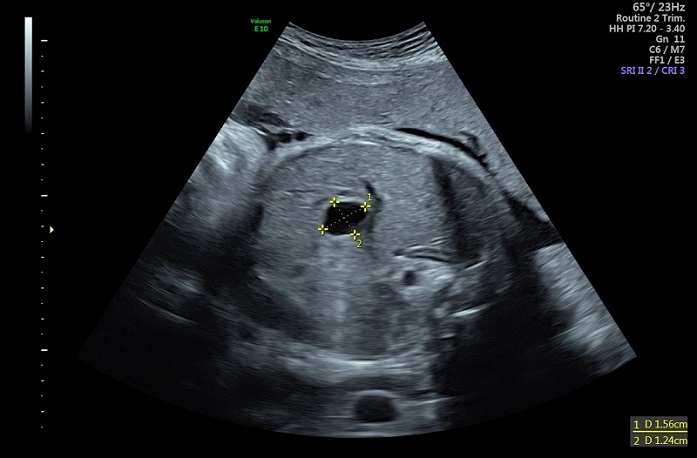

Lactante de 1 mes y 27 días derivada a la consulta de Digestivo Infantil para seguimiento de quiste hepático congénito simple. En la ecografía del segundo trimestre, realizada en su hospital de origen, se objetiva una imagen quística a nivel abdominal. Por este motivo es derivada a nuestro centro, donde, en la semana 25, se realiza nueva ecografía que muestra datos sugestivos de quiste de colédoco: imagen quística de 9 x 9 mm de diámetro que se localiza en hemiabdomen derecho fetal, inmediatamente por encima de la vesícula biliar, contactando con ella en su porción más superior (Figura 1).

| Figura 1. Quiste hepático congénito. Ecografía prenatal en la que se visualiza una imagen quística abdominal |